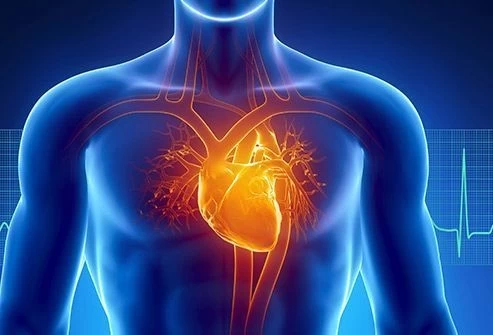

قلب یکی از مهم ترین اعضای بدن است که وظیفه انتقال خون به انواع اعضای بدن را دارد. میتوانید تصور کنید اگر قلب کار نکند چه اتفاقی می افتد؟ در این پست ما به انواع ناراحتی قلبی، علائم آنها، چگونگی رفتار با شخصی که ناراحتی قلبی دارد و اینکه ناراحتی قلبی چه هست می پردازیم. پس تا آخر با من همراه باشید!